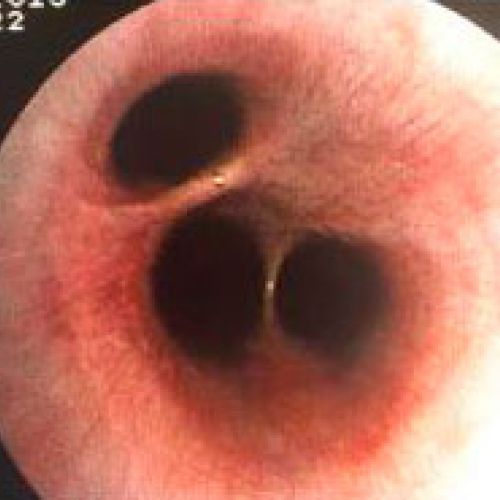

Endoscopia rígida y endoscopia flexible

En CiruVET realizamos procedimientos diagnósticos, como las endoscopias de última generación

En CiruVET contamos con el equipo necesario para los diferentes procedimientos diagnósticos y terapéuticos a nivel respiratorio y digestivo. En resumen, realizamos las siguientes pruebas diagnósticas: